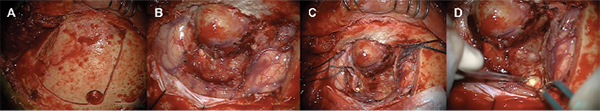

Tras realizar la craneotomía frontal, se objetivó la integridad de la duramadre de la convexidad frontal y se identificó una lesión de características óseas en el interior del seno frontal compatible con osteoma. La apertura dural permitió reconocer una voluminosa lesión de bordes bien definidos, encapsulada, en aparente continuidad con la pared interna del seno frontal izquierdo. Dicha lesión, compatible con mucocele intracerebral, presentaba una ruptura en su vertiente posteromedial (Fig 2.) Del interior de la lesión encapsulada se obtuvo material mucoide/proteináceo que fue remitido para estudio microbiológico y anátomo-patológico. La colección fue resecada conservando la cápsula y posteriormente remitida para cultivo. Una vez aislada la lesión del parénquima cerebral, se procedió a su exéresis en bloque confirmando su continuidad con el interior del seno frontal izquierdo a través de un defecto dural frontobasal y óseo de la pared posterior del mismo (Fig 3).

Completada la exéresis de la lesión intracraneal, se procedió a la resección del osteoma intrasinusal frontal y preparado del seno para su sellado y reconstrucción. La consistencia del osteoma sinusal permitió su fresado con motor quirúrgico de alta velocidad y su exéresis hasta identificar el ostium a nivel mediobasal. La mucosa remanente en el interior del seno, de predominio posterior, fue resecada exhaustivamente hasta visualizar las superficies óseas intrasinusales de la pared externa del seno frontal y resto de pared interna. Finalizado el vaciado del seno frontal, se puso de manifiesto el defecto de la pared interna del mismo y la solución de continuidad de la duramadre frontobasal.

La reconstrucción y sellado del seno frontal se llevó a cabo con cemento artificial (Mimix-Walter Lorenz Surgical, Jacksonville, FL, USA). Una vez solidificado se procedió a cubrir el seno con un colgajo pediculado de galea y periostio frontal. Aisladas las cavidades paranasales, se completó el lavado del compartimento intracraneal y se procedió al cierre hermético de la duramadre frontal, reposición ósea y cierre por planos (Fig 3).

Fig 2. Imágenes intraoperatorias. A) Incisión pterional modificada con abordaje frontotemporal izquierdo. B-C) Disección microquirúrgica con exposición de lesión frontal basal (mucocele intracraneal) y osteoma frontal intrasinusal D) Colección abscesificada posteromedial al mucocele intracraneal.

Fig 3. Imágenes intraoperatorias. A) Osteoma frontal. El disector indica el punto de ruptura de la pared del seno y entrada del mucocele a la cavidad intracraneal. B) Fresado y vaciado del seno frontal izquierdo. El disector muestra la solución de continuidad C) Comunicación entre el seno frontal y el lecho del mucocele. D) El disector indica el defecto óseo de la pared posterior del seno frontal y el defecto dural frontobasal. E) Retracción fronto-basal y exposición del techo de la órbita. F) Sellado del seno frontal tras vaciado y exéresis de los restos de mucosa.